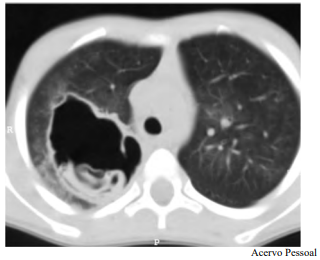

Determinado paciente de 49 anos de idade, morador em zona rural, iniciou com quadro de tosse importante, com piora progressiva, de início há dois meses, associada a alguns episódios de vômica. Refere febrículas na última semana. O paciente é tabagista leve, trabalha com criação de ovelhas e mora em casa com cachorros e gatos. Nega viagens internacionais recentes. Não foi encontrada nenhuma alteração no exame físico. Verificaram-se FC = 80 bpm, FR = 20 irpm e SatO2 = 99% em ar ambiente. A tomografia de tórax apresenta uma lesão cística de paredes espessas e conteúdo heterogêneo em seu interior, conforme representado na imagem a seguir.

Tendo em vista esse caso clínico e os conhecimentos médicos correlatos, julgue o item a seguir.

Formação de empiema ou fístula do cisto com o brônquio é uma complicação possível desse caso.